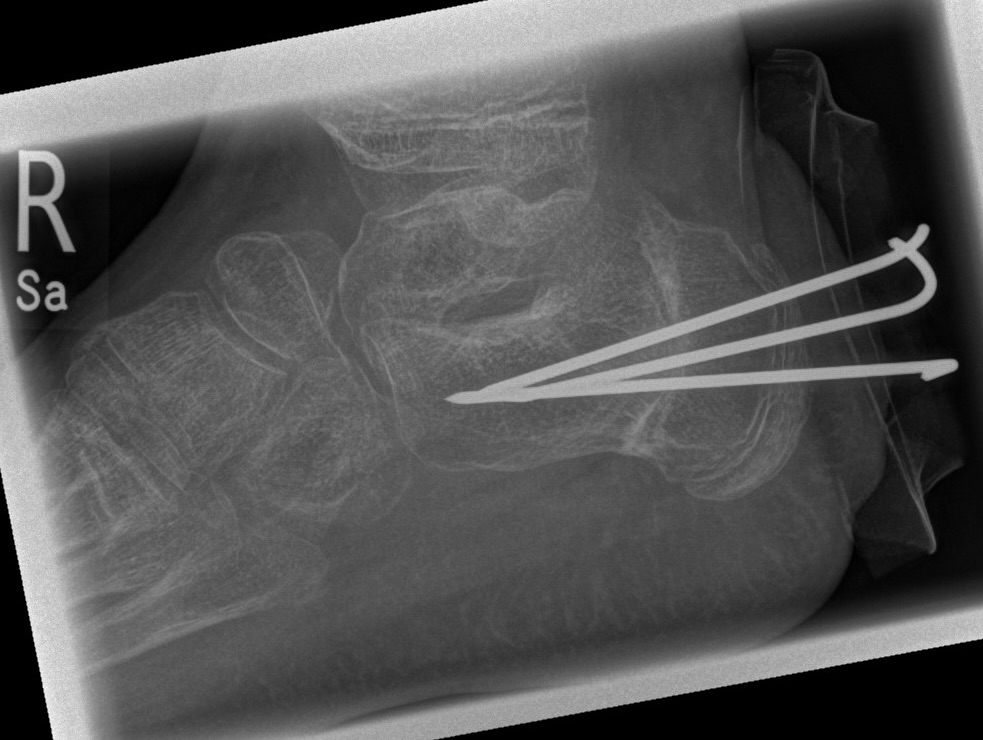

Zusätzlich schränken Wachstumsfugen die Wahl der Osteosynthese ein. Eine die Fuge kreuzende Osteosynthese ist ausschließlich mit Kirschner-Drähten möglich (Abb. 3).

Abb. 3 a-j: Beispiel einer Calcaneusverschiebeosteotomie mit offenen Wachstumsfugen und der entsprechenden Osteosynthese mit Kirschner Drähten. Lokalisation der Osteotomie (a), Lage der Fräse (b-d), Drahtlage mehrere Ansichten (e-h), Heilung der Osteotomie 4 Wochen postoperativ und Entfernung der Drähte (i-j).

Calcaneus-Osteotomie

Die minimalinvasive Calcaneusverschiebeosteotomie bietet eindeutige Vorteile gegenüber dem offenen Verfahren, sodass wir bei Kindern und Jugendlichen nahezu keine offene Verschiebeosteotomie mehr durchführen. Am Calcaneus liegt die offene Wachstumsfuge dorsal. Bei der Durchführung müssen Schenkel der V-förmigen Osteotomie daher etwas steiler angelegt werden, in einem stumpfen Winkel (siehe Abb. 3 a-j). Für die Osteotomie liegen unsere Patienten auf dem Rücken und der BV wird für die exakte Seitaufnahme eingestellt. Der Fuß lagert auf einem hohen OP-Kissen und die Osteotomie kann bequem mit einem langen Kirschner-Draht und einem sterilen Stift angezeichnet werden (Abb. 15).